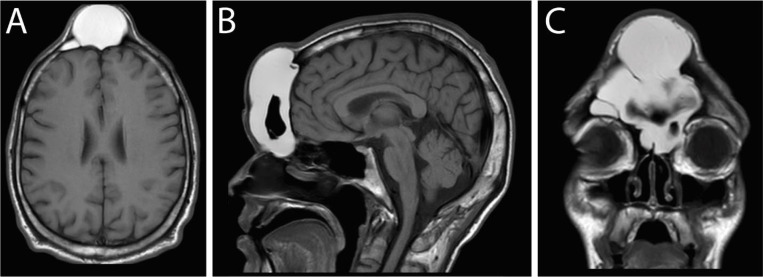

Mucocele is a benign soft tissue mass that could occur in all accessory glands. Mucocele can also occur in paranasal sinuses. It is mostly placed in the frontal sinus and barely grows larger than 1.5 centimeters(cm). Based on the affected site, it could cause facial pain and headache. Analgesics like opioids could relieve and potentially make patients ignore the headache and cause giant frontal mucocele. This article discusses a patient with giant frontal sinus mucocele (7×8×8 cm) and opium addiction that presented with severe and intolerable pain. A 32 yr old man came to Rajaee Trauma Hospital, Shiraz, Iran with a severe headache and a large swelling of the face frontal region that developed gradually. In physical examination, the mass was non-tender, non-pulsatile, and free from the overlying normal skin. Computed tomography (CT) scan and magnetic resonance imaging (MRI) demonstrated a frontal sinus mucocele. The operation was planned, and the patient was discharged after two days. Subsequently, the 6-month follow-up of the patient was normal. Two different hypotheses are declared in this article. First, the potential role of opium addiction as a risk factor for giant mucoceles was noted, then the analgesic non-responsiveness of sinus mucoceles was described. The latter hypothesis is more likely. So, we should consider that if the patient had an analgesic-resistant headache, one differential diagnosis could be sinus mucocele. Moreover, the pos sible psychological effect of addiction on discounting face beauty was acknowledged.